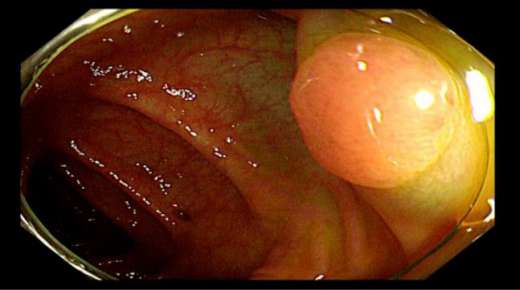

距肛門16cm直腸白光下較大息肉在檢查過(guò)程中我們發(fā)現,C先生在升結腸回盲瓣附近、橫結腸、直腸等部位多發(fā)息肉,個别息肉較大,甚至達到1.5cm以上。且通過(guò)NBI技術進(jìn)行觀察,息肉已經(jīng)有了病變的不良趨勢。

橫結腸白光下息肉,基底部給予亞甲藍生理鹽水黏膜下注射後(hòu)拟行EMR(内鏡下黏膜切除術)術